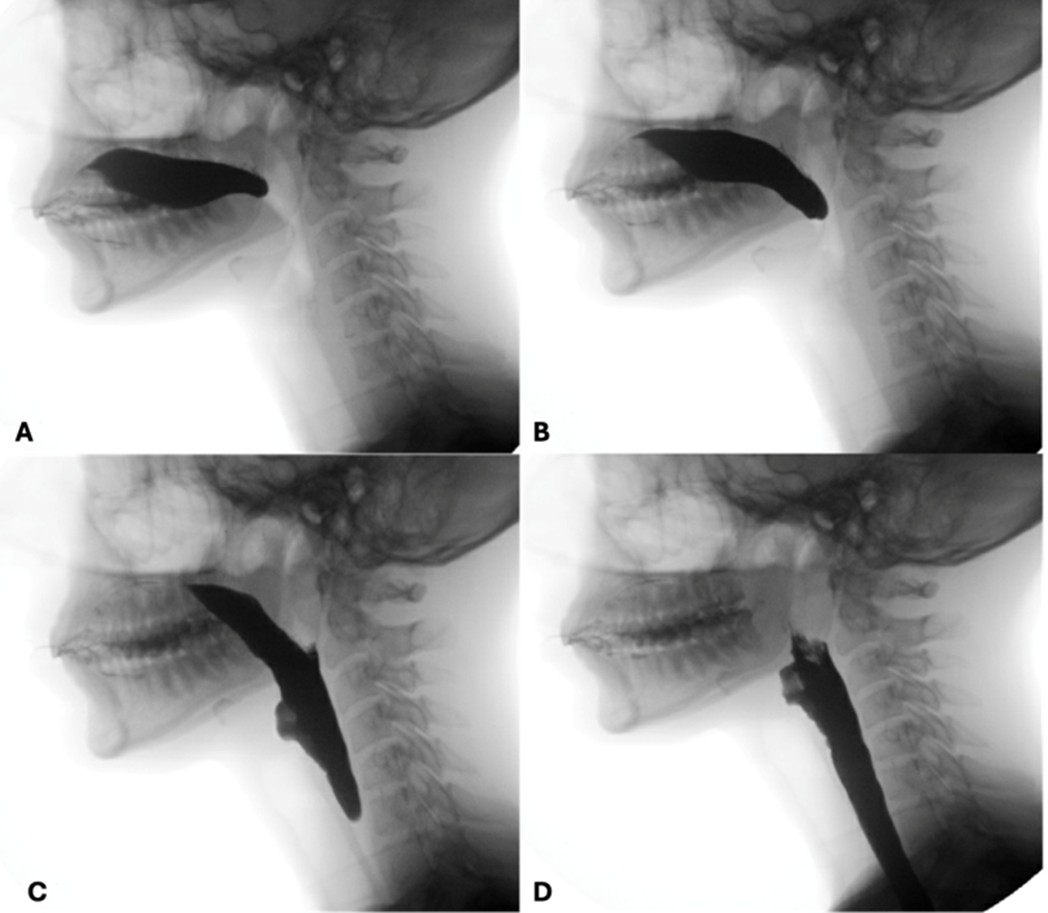

The preparatory phase of deglutition applies exclusively to the deglutition of solid food and boluses are prepared through a three-stage process that occurs simultaneously17: phase I transport - the tongue performs rotational movements to displace food posteriorly and laterally onto the occlusal surface of postcanine teeth; food processing - mastication and mixture of food with saliva alters the consistency of the boluses and prime it for swallowing; and phase II transport - processed food is pushed to the oropharynx, where it aggregates before being swallowed. By combining clinical and radiological evaluations, defects such as prolonged food processing time or reduced tongue movements can be identified. (Fig. 3)

Figure 3: Preparatory phase of a solid bolus shows mastication (A) followed by phase II transport to the oropharynx (B and C) before swallowing (D)